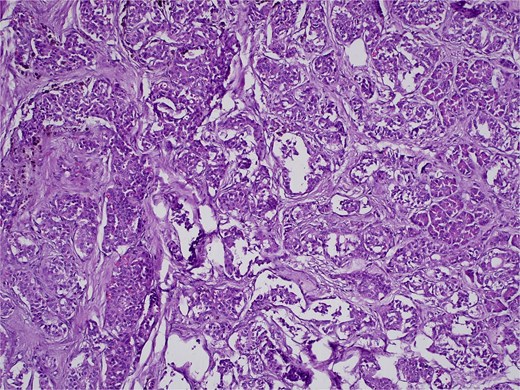

On 27 January 2025, the patient underwent a Whipple procedure (pancreaticoduodenectomy). The surgery included cephalic pancreatectomy with reconstruction through hepaticojejunostomy and gastrojejunostomy in a Roux-en-Y configuration. Gross pathology revealed a firm, white-yellow, indurated mass in the pancreatic head measuring 3.7 × 3.5 × 3 cm with irregular borders and central hardness (Fig. 4). Histopathological analysis confirmed a Grade 1 neuroendocrine tumor (insulinoma), with a Ki-67 index of 2%. The tumor showed direct extension to adjacent pancreatic tissue, the duodenal muscularis propria, the adventitia, and the muscularis of the common bile duct. Five peripancreatic lymph nodes were dissected, three of which were positive for metastases (Figs 5–9).

H&E stain, 100× magnification. Diffuse infiltration of pancreatic parenchyma by tumor cells with desmoplastic stroma.